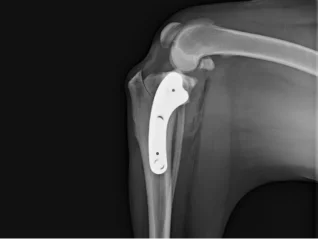

Total Joint Replacement

View PathwayTrauma & Fracture Repair